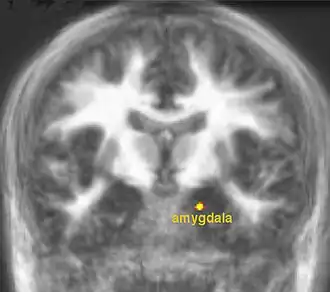

The lateral hypothalamus sends control signals to the VTA that are involved in regulation of eating behavior. The VTA and hypothalamus send regulatory signals to other brain regions such as the nucleus accumbens, orbitofrontal cortex (OFC) and the amygdala (Figure 8) that are important for control of human eating behavior, particularly in the context of learned patterns of food consumption that develop over a lifetime (see Piech et al.). For humans, Farooq et al. showed that leptin can modulate how the nucleus accumbens responds in test subjects who experience a desire to consume food, with the observed human brain activity changes corresponding to leptin-induced reduction in appetite.

Summary. Hunger plays a fundamentally important role in regulating human eating behavior. The brain can sense circulating levels of nutrients such as glucose and respond to satiety-producing hormones such as leptin. Other hormones such as grelin promote appetite. The aversive sensations associated with hunger can be produced by physiological processes such as the empty stomach being stimulated to contract. Sensory nerves carry appetite-enhancing signals to the hypothalamus and hormones such as leptin and ghrelin bind to receptors on neurons in the hypothalamus and regulate their activity. The hypothalamus acts as regulatory center for receiving orexigenic and anorexigenic signals. The hypothalamus is linked by axonal connections to other parts of the brain (such as the nucleus accumbens) that allow for reflexive control of eating in newborns. The hypothalamus is linked to other brain regions such as the amygdala and the ventral tegmental area that allow people to learn how to avoid hunger. People are usually able to learn patterns and habits of eating that are appropriate for our environment and that allow us to maintain a healthful body weight. Most research into hunger and satiety is related to health-endangering patterns of eating behavior such as under-eating and over-eating that leads to obesity.